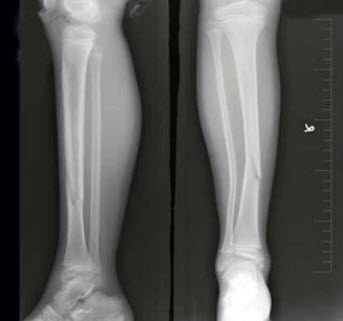

198、单项选择题

女,8岁,外伤后致右胫骨骨折,如图所示,下列描述正确的是()

A.对位好,对线差

B.对位差,对线好

C.对位对线好

D.对位对线差

E.以上均不正确